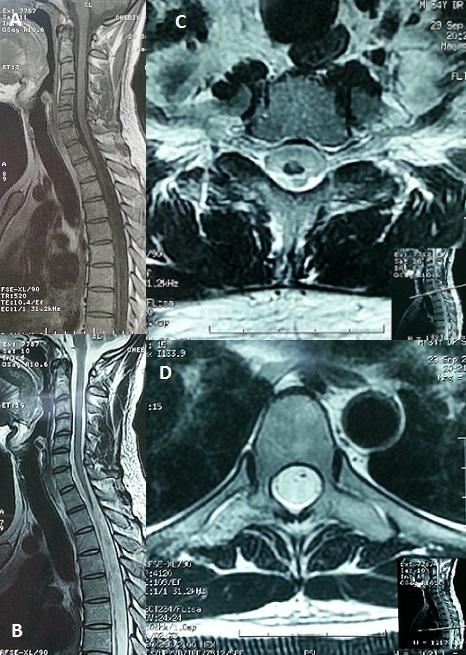

[A case of spinal cord atrophy in a professional diver].

https://cdn.ncbi.nlm.nih.gov/pmc/blobs/e4b6/4747442/5d18d48488ee/PAMJ-22-169-g001.jpg